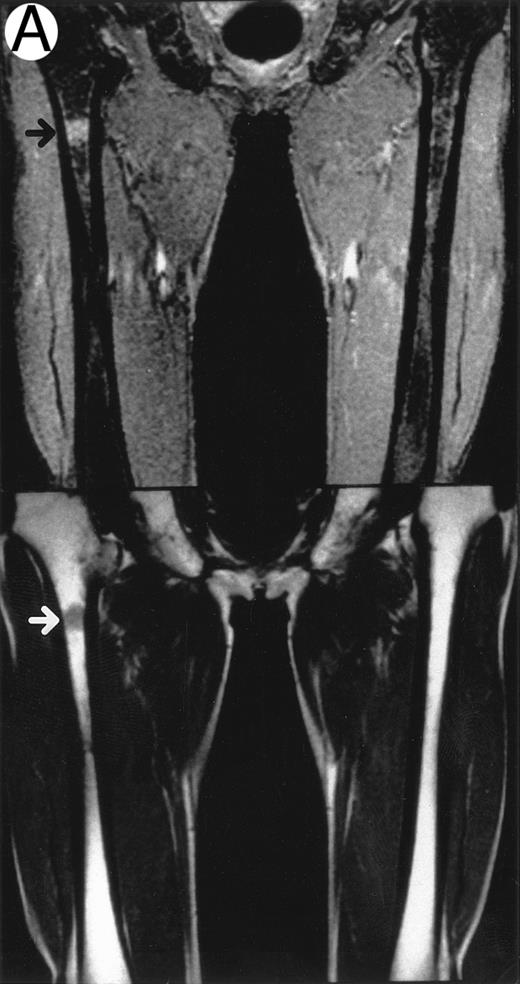

MRI.MRI was performed using SE sequences with the whole-body coil in a 1.5 tesla superconducting system (MRT 200FX/II; Toshiba, Tokyo, Japan). Coronal T1-weighted SE images of the femur were obtained in contiguous 10-mm slices in a 256 × 256 matrix with TR, 400 ms; TE, 20 ms; and number of signal acquisitions, 2. Tissues with short proton T1, such as fatty tissue, have a high signal intensity and appear bright on T1-weighted SE images, whereas those with a long T1, such as cellular marrow, have a low signal intensity and appear dark. STIR coronal images of the femur were obtained in 10-mm slices in a 256 × 256 matrix with TR, 1,500 ms; TE, 20 ms; and TI, 150 ms. On STIR images, the signal from fatty tissue is eliminated, whereas the signal from tissues with a longer T1 is progressively brighter. The MRI results were evaluated blindly by two independent observers who had no knowledge of the patients' marrow histology, tumor type, or stage. The MRI was classified as positive when both observers classified the T1-weighted SE images and STIR images as abnormal. The positive findings on femoral marrow MRI were categorized as follows: nodular pattern, characterized by nodular areas of fatty marrow replacement with a signal intensity that was lower on T1-weighted SE images (higher on STIR images) than that of muscles; scattered pattern, characterized by multiple scattered foci of marrow replacement on a background of uninvolved marrow; and uniform pattern, characterized by a uniform replacement of fatty marrow (Fig 1).

Patterns observed on femoral marrow MRI. (A) Nodular (arrow), (B) scattered, and (C) uniform. Top: STIR images and, bottom: T1-weighted SE images.

MRI patterns of femoral marrow.MRI findings of the femoral marrow were classified into three patterns as shown in Fig 1. Of 29 patients with a positive MRI, 21 (72%) exhibited a scattered pattern (Fig 1A), 6 patients (21%) demonstrated a uniform pattern (Fig 1B), and 2 patients (7%) exhibited a nodular pattern (Fig 1C). Of the 17 patients with positive results on BM biopsy, 11 demonstrated a scattered pattern on the MRI, and 6 patients showed a uniform pattern.